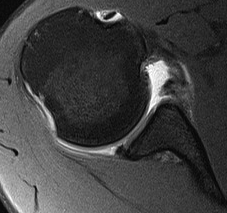

Anterior labral tears

Bony bankart / anterior glenoid deficiency